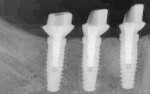

Following 3 months of healing, all the implants were found to be healing well (Figure 1). At least 1 mm of the abutments were exposed above the gingiva circumferentially. The tightness of the BellaTek Encode Healing Abutments was verified using a 0.048 hex hand driver, and radiographs confirmed that the abutments were completely seated (Figure 2). Full-arch impressions of both arches were made, using trays filled with medium-body polyether impression material (Impregum™ F, 3M ESPE, www.3MESPE.com). Light-body polyether impression material (Permadyne™, 3M ESPE) was syringed around the healing abutments. The impressions were inspected for defects in the area of the healing abutments (Figure 3). A softened wax was used to make an occlusal registration. These records were sent to the dental laboratory with a completed lab prescription.

The CAD/CAM abutments were placed on the implants, and prosthetic screws were hand-tightened (Figure 14). Full seating was confirmed radiographically (Figure 15). After proper abutment seating was confirmed, Gold-Tite® Abutment Screws (Biomet 3i) were torqued to 20 Ncm using a torque driver. The PFM crowns were placed, and radiographs were taken to confirm their full seating (Figure 16). The crowns were cemented in place (RelyX™, 3M ESPE) (Figure 17), and all excess cement was meticulously removed.